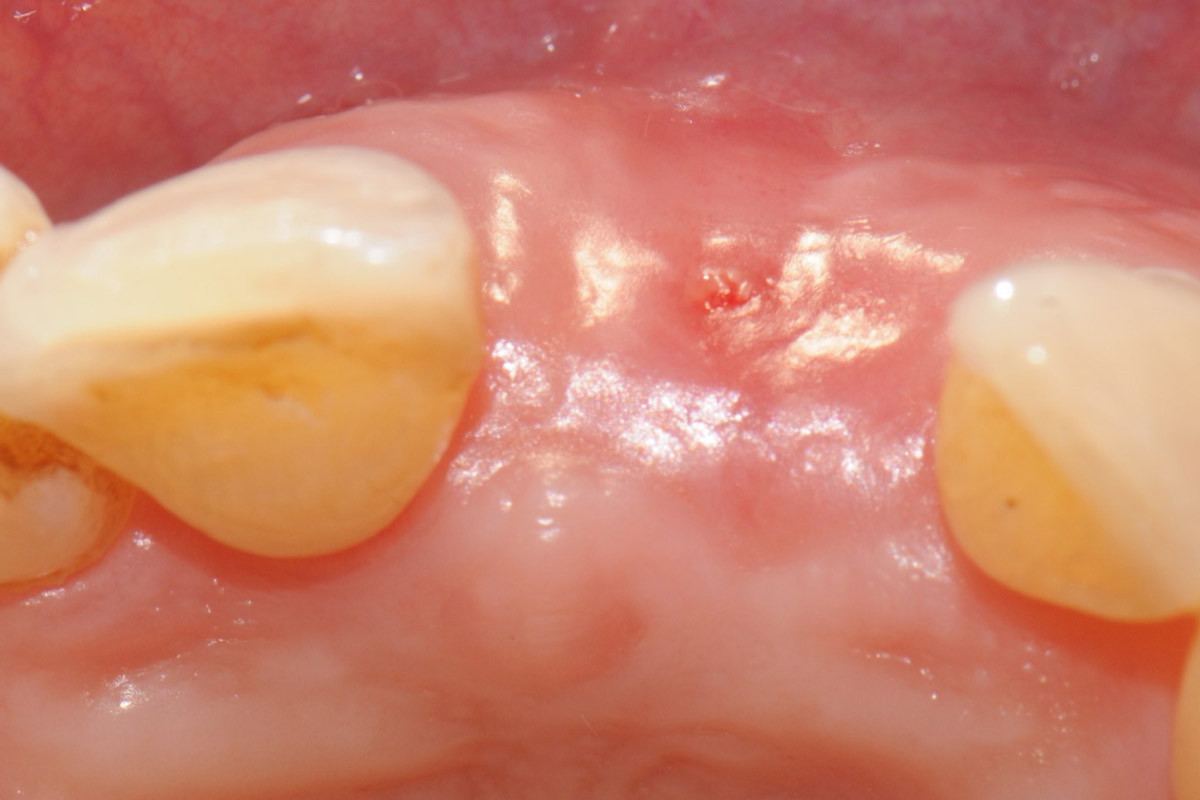

Longitudinal fracture on the root resected tooth 21 with visible buccal fistula

Tooth extraction due to root fracture